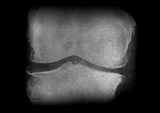

まず問診や触診を行った上で、関節のすき間や変形などの状態を調べるレントゲン(X線)検査が行われます。このとき診断によく使われるのが、変形性ひざ関節症の重症度を示すグレードという指標。グレードは1から4までに分けられており、2以降が変形性ひざ関節症と診断される基準です。グレード2が初期、3が進行期、4が末期と対応しており、進行に伴って関節の隙間が狭くなったり、骨が大きくとがる骨棘(こつきょく)ができたりします。

Kellgren-Lawrence分類(K-L分類)

変形性ひざ関節症が疑われる状態。大きな変化はないが、骨棘(こつきょく)や骨硬化(こつこうか)が見られることがある。